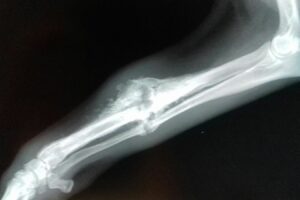

Im Rahmen der Kastration wurde auch Ricardas rechtes Vorderbein geröntgt. Die italienischen Tierärzte möchten nicht mehr daran rühren, aber wir lassen die Röntgenaufnahmen noch in Deutschland von einem Spezialisten für Orthopädie begutachten und hoffen, dass der lieben Hündin doch noch geholfen werden kann!